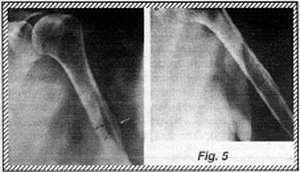

One of the most common questions I am asked is regarding the deltoid tubercle of the humerus. This tubercle is the region of insertion of the deltoid muscle onto the humerus. Generally it is not well visualized, however in some persons it can be very prominent. It generally appears as an irregularity in the contour of the cortex at the lateral proximal aspect of the humeral shaft (Fig. 4). At times however, this area can appear bubbly or cystic, with thickening of the cortex giving the humerus an expanded appearance. Frequently, a strange web-like pattern of sclerotic trabecular densities can be seen just underneath the cortical margin (Fig. 5). Similar changes are found at the insertion of the major pectoralis muscle along the crest of the major tubercle, slightly more proximal to the deltoid tubercle (Fig. 6).